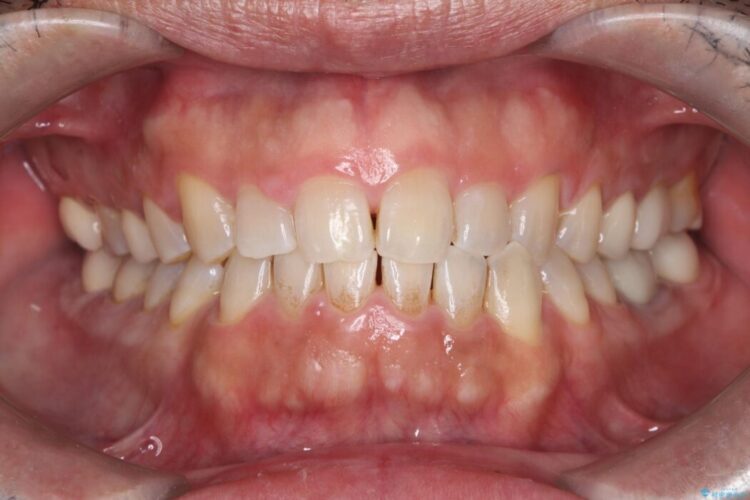

メタルフリー|全ての銀歯をセラミックへ

メタルフリー|全ての銀歯をセラミックへ ビフォー メタルフリー|全ての銀歯をセラミックへ アフター

口腔内の銀歯を全て無くし、白く健康的な状態にしたいとご来院された患者様です。